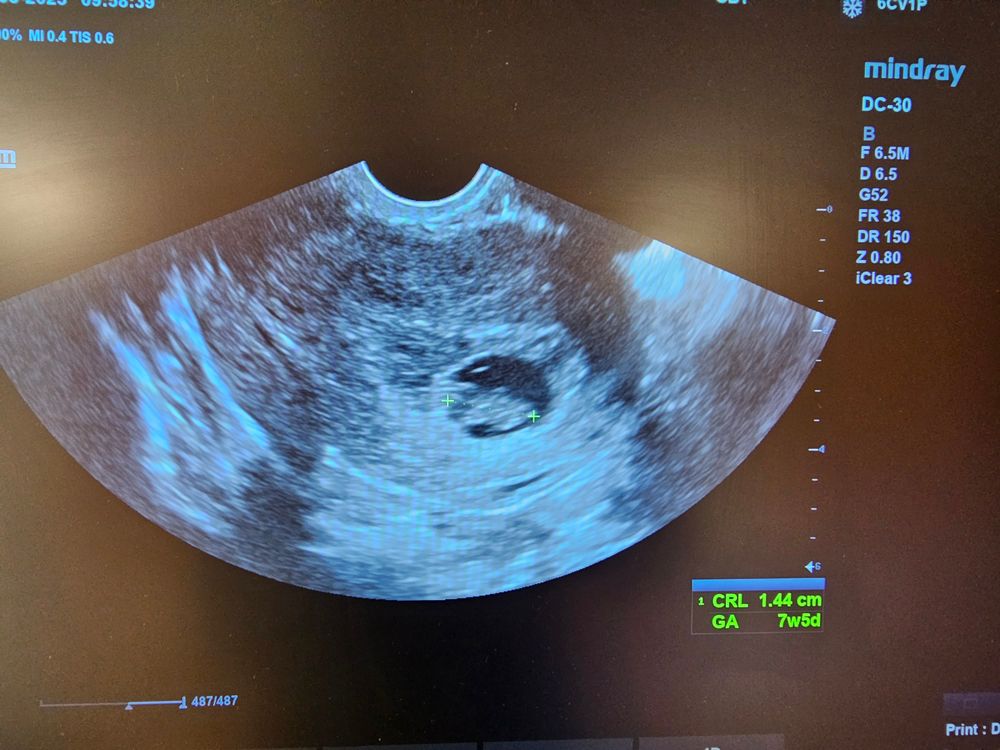

28.07 пошла в больницу на осмотр, во время осмотра коричневые выделения полились. Прописали дюфастон (10 дней) и транексам (4 дня). Сердце малыша билось, но врач сказала, что может быть угроза выкидыша. Договорились, что если с лекарствами выделения все равно будут, то вернуться в клинику.

4.08 Вчера сходила еще раз в клинику, осмотрели, все нормально с малышом - сердцебиение есть, выделений стало меньше. Но, подумав, что все хорошо, решили с молодым человеком аккуратно заняться любовью. Конечно, потом коричневые выделения (оно и логично). П.с. до этого сдерживались, хотя врач не запретил.